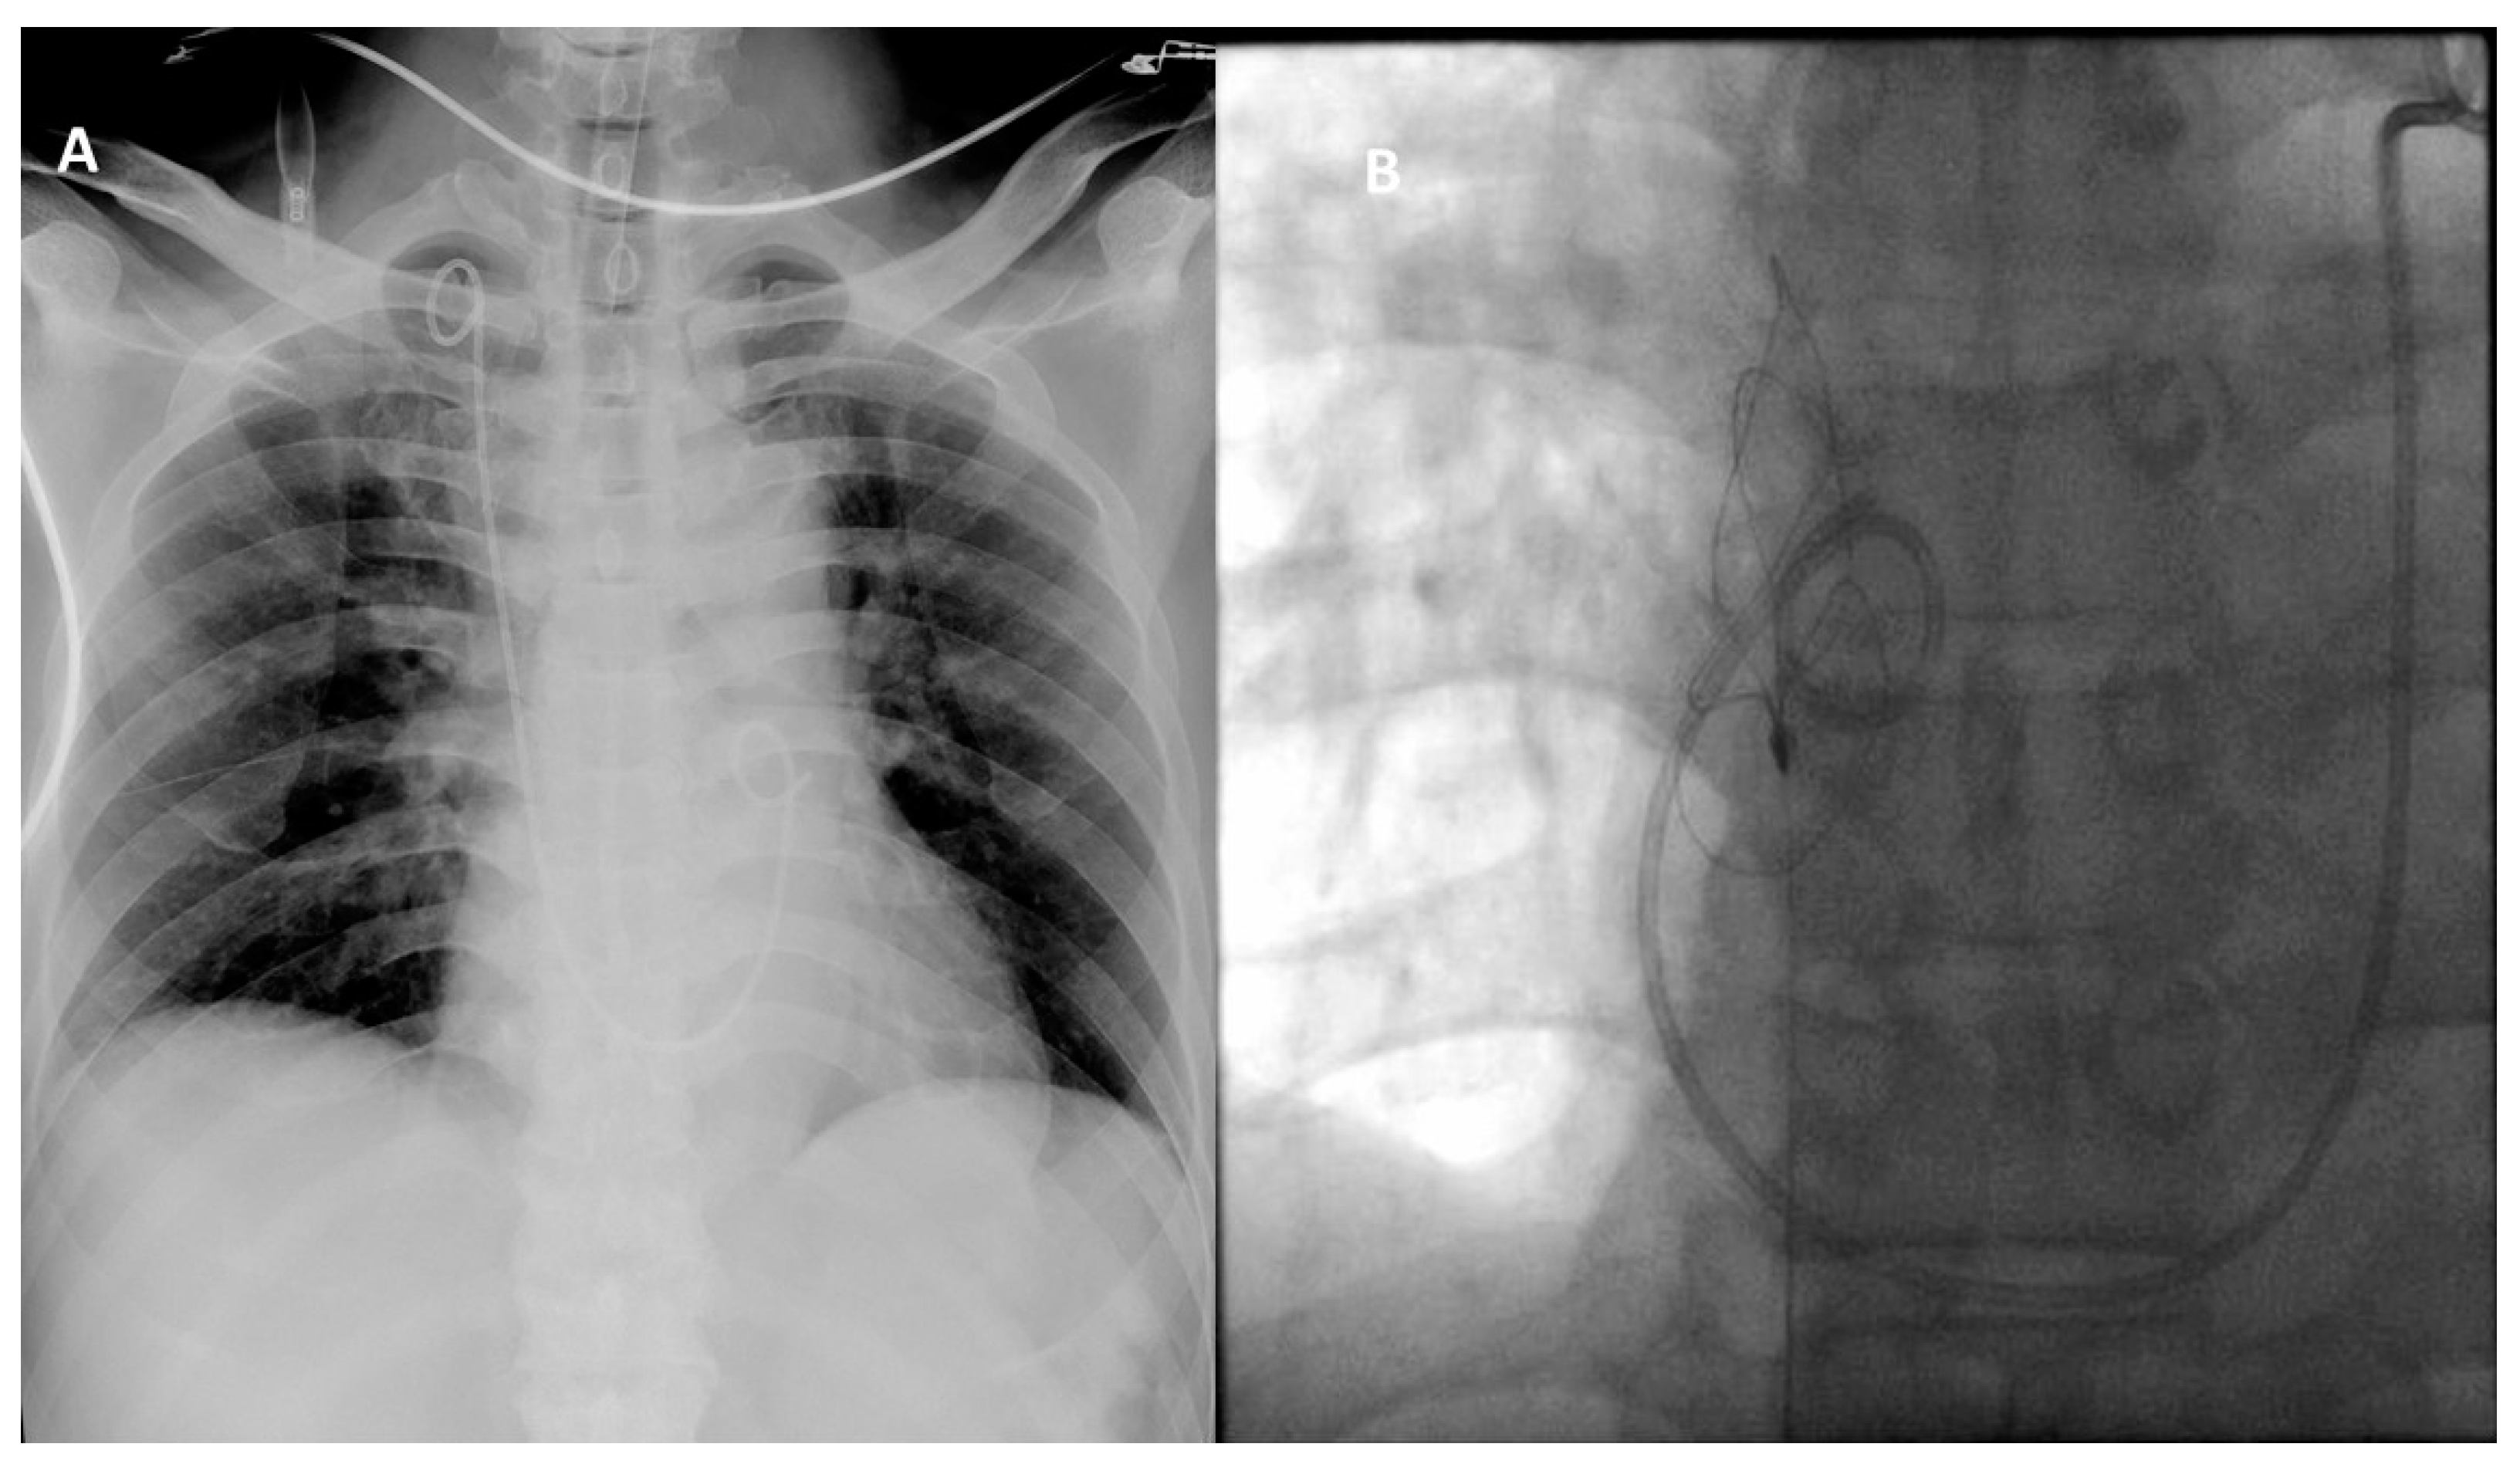

2. Case Presentation